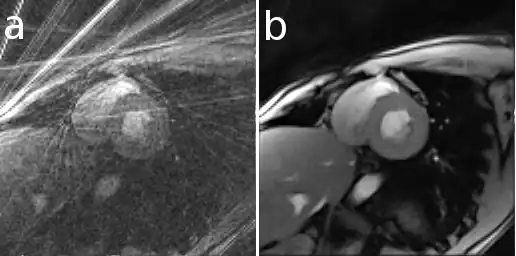

Here is an example that illustrates the benefits of iterative image reconstruction for cardiac MRI.[21]